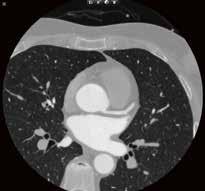

65-jähriger männlicher Patient; Abb. links: Notaufnahme Röntgen Liegendthorax bei Verdacht auf COVID-19-Pneumonie, Abb. rechts: CT-Bestätigung der COVID-19-Pneumonie am gleichen Tag.